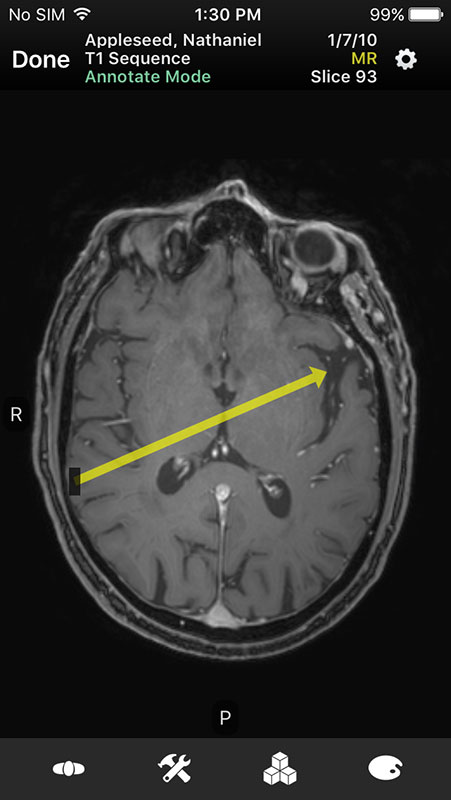

These sample images feature same imaginary patients and cases from the Mobile MIM app and contain X-ray, PETCT, MR, and ultrasound scans, alongside the name of the procedure.

Just like in Mobile MIM app, images open in multi-planar view allowing users to choose series depending on the type of imaging technique, add annotation, or measure the image.